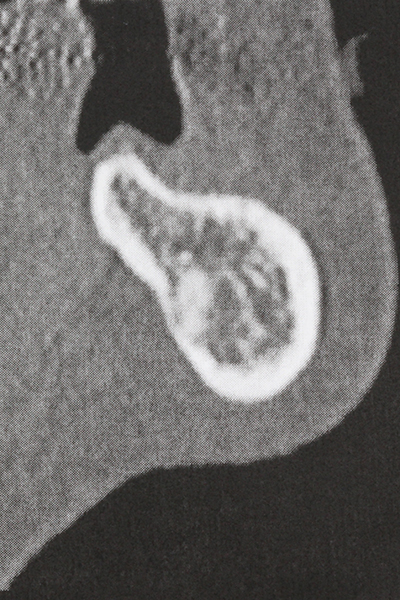

La preparación de la ventana lateral en la elevación del suelo del seno maxilar representa un enorme reto, sobre todo para profesionales de la implantalogía que tienen poca experiencia en técnicas quirúrgicas. Retirar la cobertura ósea del seno maxilar sin provocar daños en la membrana de Schneider es tan solo una parte de la operación; tras crear un acceso suficiente, es preciso movilizar con cuidado la mucosa del seno maxilar a fin de dejar espacio para el material o los implantes que vayan a incorporarse. En esta aplicación la cirugía piezoeléctrica resulta útil en dos sentidos: por un lado, el uso de insertos diamantados permite realizar una retirada selectiva del hueso y, si se actúa con cuidado, la membrana permanece intacta, y por otro lado, las frecuencias de ultrasonidos favorecen también un desprendimiento sin problemas de la membrana, pues se transfieren al espacio comprendido entre la mucosa y el suelo del seno maxilar gracias al uso de piezas romas especiales (Cassetta, Ricci et al. 2012, Pereira, Gealh et al. 2014) (Rickert, Vissink et al. 2013). De este modo, no es de extrañar los trabajos publicados en la actualidad sobre la técnica de elevación del suelo del seno maxilar mediante la técnica de Caldwell-Luc con instrumentos piezoeléctricos (Wallace, Tarnow et al. 2012).